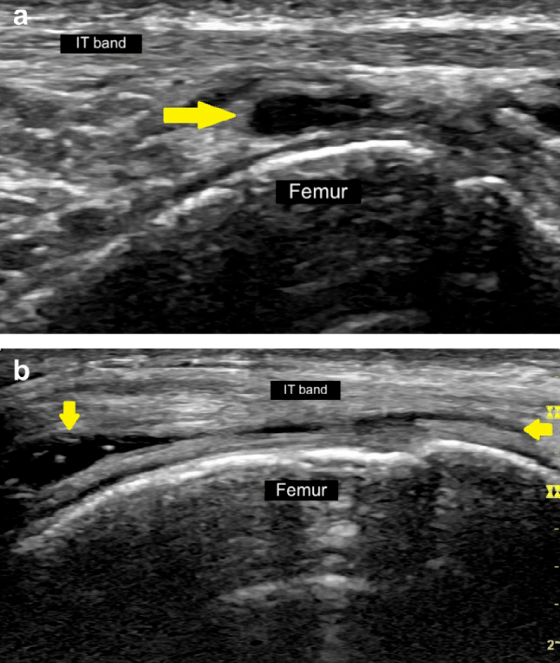

髂胫束综合征或摩擦综合征是膝关节外侧过度使用的疾病。它在运动员(例如跑步和自行车)群体中高发。超声影像作为一种高性价比的成像方式,能够以高分辨率、动态评估以及与对侧健康侧进行比较来显示浅表软组织结构,对于评估髂胫束综合征具有重要参考价值。

- 髂胫束深处的脂肪和结缔组织受压

- 髂胫束下方的外膜囊的慢性炎症

- 关于第一点的“摩擦说”:与髂胫束在涉及重复膝关节屈伸的活动中来回摩擦股骨外上髁有关,从而导致髂胫束摩擦和邻近软组织发炎。多年来,这一病因一直存在争议,特别是关于髂胫束运动的方向和程度。然而,一项超声研究表明,在膝关节伸展和屈曲期间,髂胫束相对于股骨外上髁沿前后方向移动,因此支持摩擦作为病因学因素的核心作用。